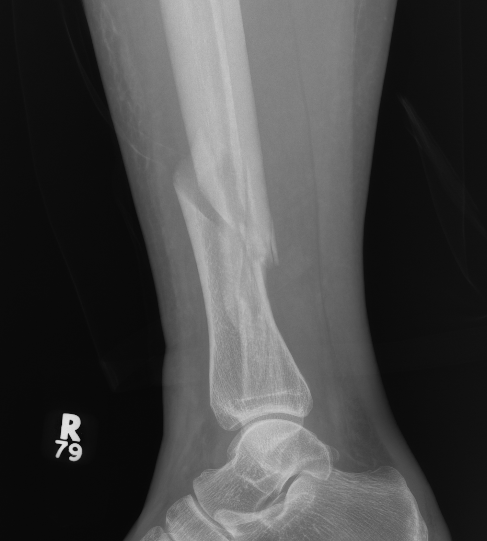

Posterior Malleolar Fractures

- occult in 70%

- especially with spiral distal tibial fractures